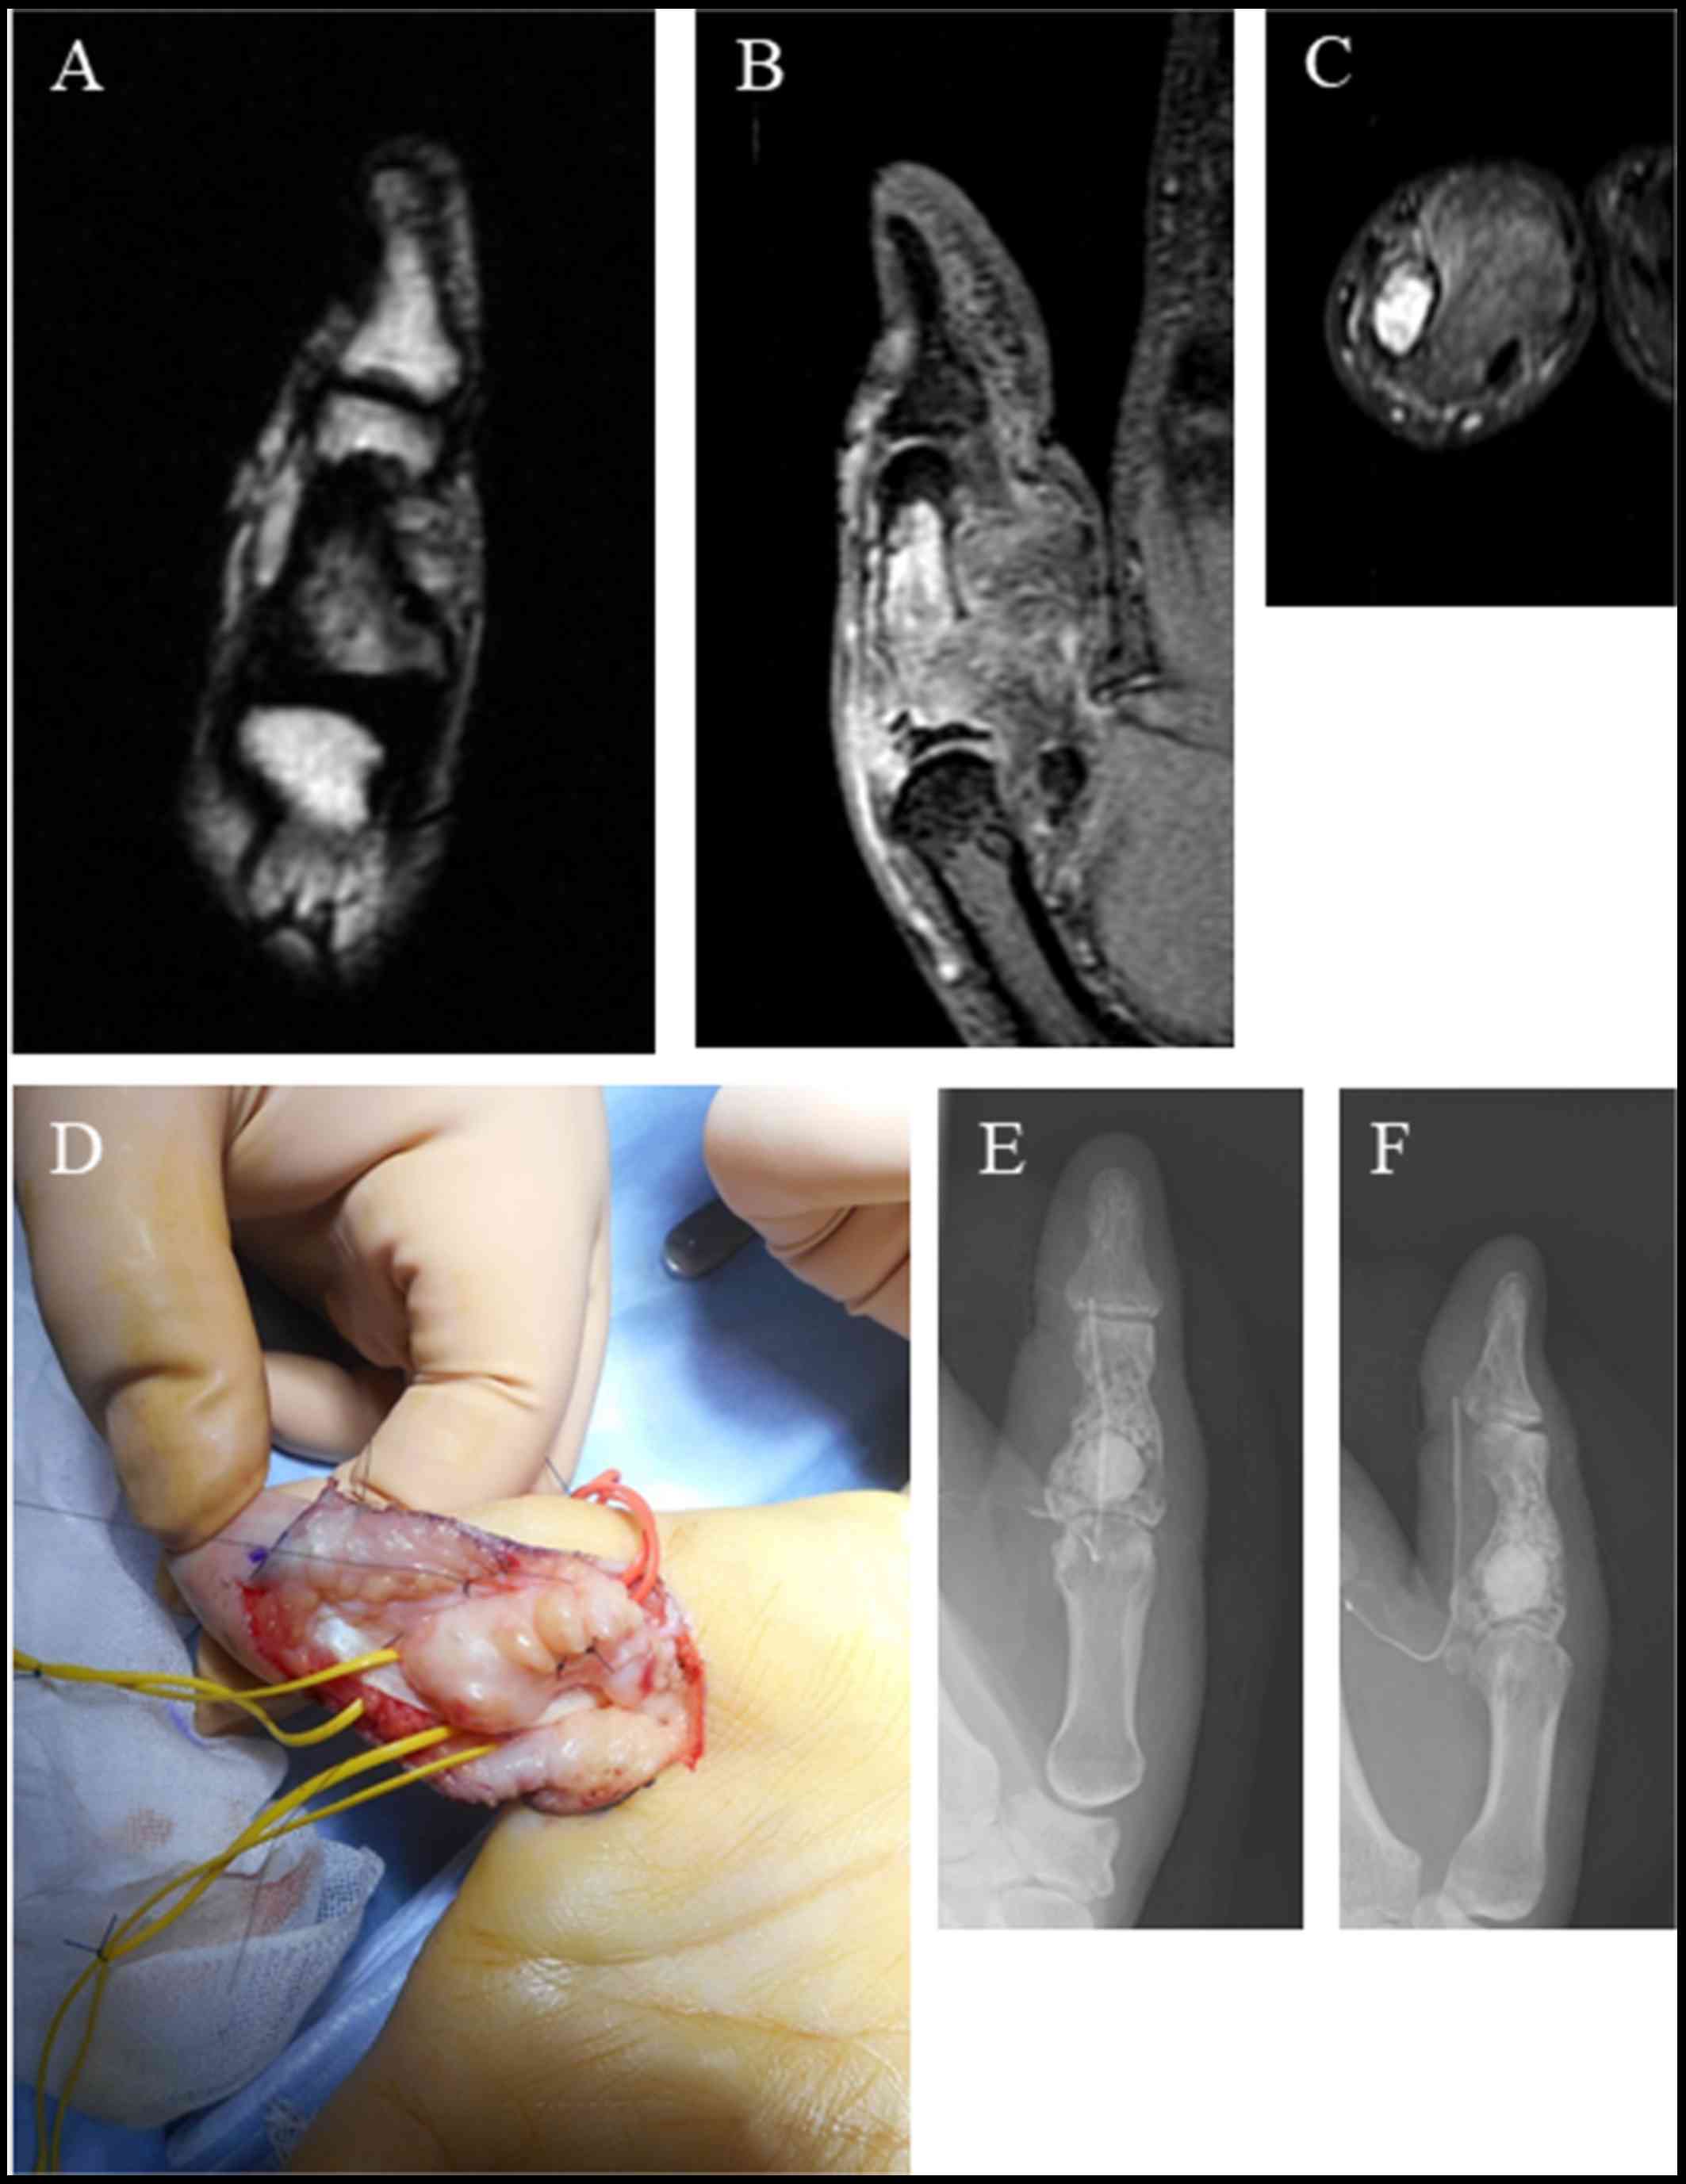

This is a case of a 47-year old woman who presented with right thumb pain and swelling (Fig. 1A and B). Her past medical history did not include any trauma or any other causative clinical condition. She also stated that there was no family history of any type of cancer. There was no limitation in the range of movement. A radiographic image showed a soap-bubble appearance, indicating bone destruction and rupture of the bone cortex of the intermediate phalanges of the thumb (Fig. 1C and D). A computed tomography (CT) image confirmed the presence of a tumor with fat concentration, bone destruction in the intermediate phalanges, and rupture of the bone cortex (Fig. 1E and F). Magnetic resonance imaging (MRI) revealed a low-intensity mass extending to the outer area of the phalangeal bone with inner mosaic intensity in a T1-weighted image (Fig. 2A). A T2-weighted image also showed a high-intensity mass with inner mosaic intensity (Fig. 2B), while a short TI inversion recovery (STIR) image showed a low-intensity mass (Fig. 2C). The tumor was resect by making a zigzag skin incision from the palm side. A further incision was made from the A 0 pulley to the A 2 pulley, and the tumor was identified by moving the flexor tendon to the side (Fig. 2D). The tumor was found adhered to the bone wall, and had expanded by destroying several bone walls. To remove the tumor, we scraped the bone wall where adhesion of the tumor was evident. The tumor had also adhered to the surrounding soft tissue. After washing, beta-tricalcium phosphate was used to fill in the bone defect (Fig. 2E and F). Sutures were placed extending from the A0 pulley to the A2 pulley. A Penrose drain was placed subcutaneously, and the subcutaneous tissue and skin were sutured. The resected tumor showed a lipomatous image profile and was elastic in texture. Hematoxylin-eosin staining of the tumor section showed both necrotic fat tissue and fibrous tissues (Fig. 3A). The immunohistochemical staining was negative for murine double minute 2 (MDM2) and cyclin-dependent kinase 4 (CDK4) (Fig. 3B and C). No obvious abnormal findings were found in postoperative blood test results (Table I). Currently, 6 months after surgery, tumor recurrence or any thumb malfunction has not been observed.

Figure 2.

Magnetic resonance imaging scan and surgical findings. T1-weighted magnetic resonance imaging (MRI) scan (A). T2-weighted MRI scan (B). Short TI inversion recovery (STIR) MRI scan (C). Surgical findings (D). Radiographic scans after surgical treatment (E and F).